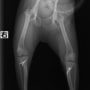

■ 症例20 ポメラニアン 8ヶ月 1.8kg

左右膝蓋骨脱臼 グレードⅢ

2ヶ月前から間欠的跛行が認められ、両膝の膝蓋骨脱臼整復術を行った。

手技は縫工筋及び内側広筋の解放、脛骨粗面の外側転位、滑車ブロック形造溝術、内外側関節包の縫縮を選択し実施した。

右側の膝蓋骨脱臼は上記手技で整復されたものの、左側はそれのみでは膝蓋骨が浮く様子が認められた。その為、PDS縫合糸にて膝蓋靱帯を1糸のみ縫合し、靱帯の縫縮を行った。

膝蓋骨脱臼は膝関節における膝蓋骨の内外側の脱臼と定義されるが、時として単純な内外の脱臼ではなく、膝蓋骨が大きく前方に浮き上がるように脱臼する場合がある。特にトイプードルやポメラニアンといった犬種に多く認められる。

内側脱臼に加えて前方への浮き上がりを矯正する為に、従来より脛骨粗面転移により膝蓋靭帯を外方と下方に引っ張り、固定する方法を選択する。膝蓋骨の前方への浮き上がりが軽度の場合は、従来法ではなく関節包の縫縮で対応していた。しかし、一部の症例で膝蓋骨の動きが悪くなり伸展機構が円滑に機能せずロボット様歩行になるケースがあった。

その為、膝蓋靭帯自体を縫縮する方法を採用した。この方法により、膝関節の伸展機構を妨げず膝蓋骨の軽度の浮きを矯正することが可能となった。

本症例の経過は良好である